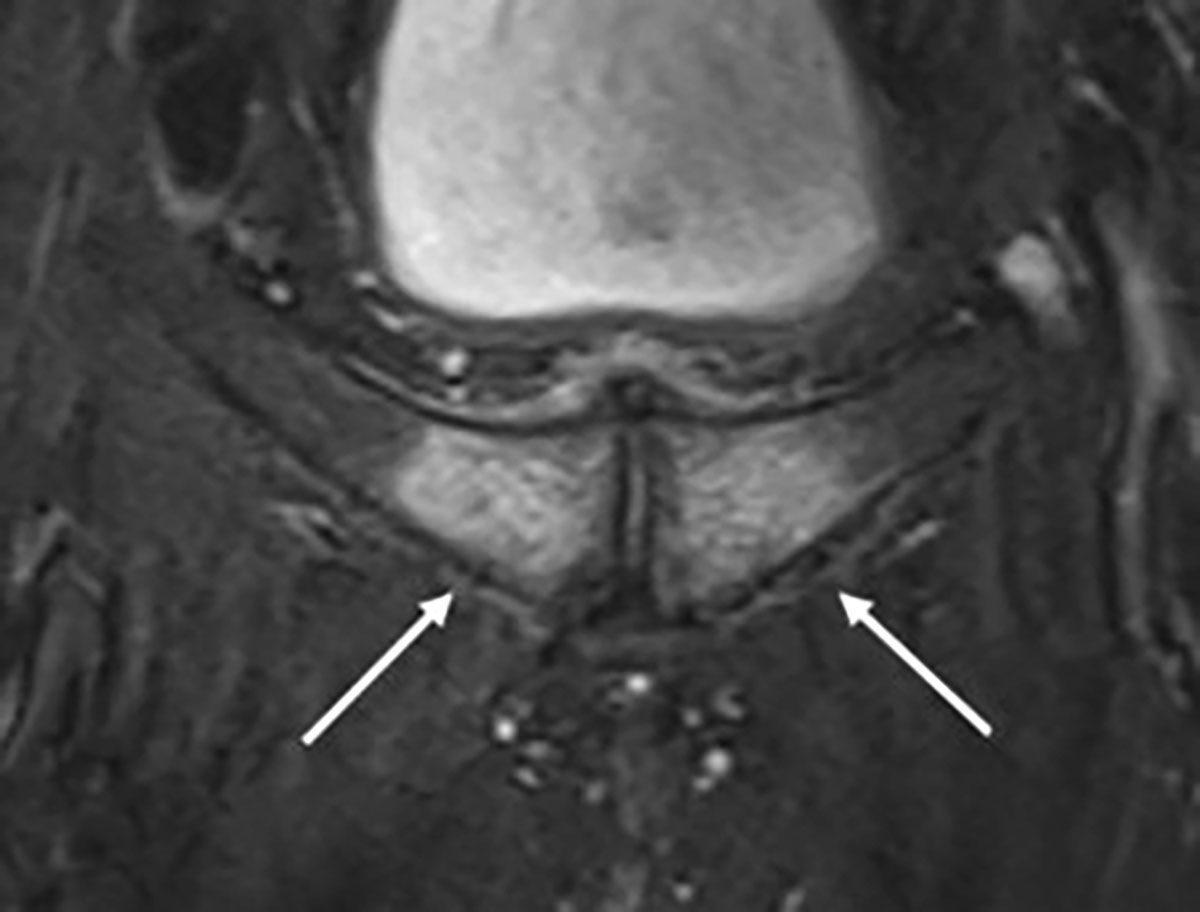

Ein 26-jähriger Eishockeyspieler bekam in einem Turnierspiel in der Defensivzone einen Check. In diesem Moment war sein linkes Knie in einer fixierten X-Bein-Stellung. Durch den Stoß wurde die valgische Kniestellung forciert verstärkt und der Spieler spürte direkt einen medial einschießenden Schmerz. Der Spieler konnte das Spiel nicht fortführen und wurde zur Untersuchung mit in die Kabine genommen. Es zeigte sich ein starker Schmerz medial am Kniegelenk im Valgusstress bei jedoch guter Bandstabilität des MCL (mediales Kollateralband) in 0° und 30° Flexion. Der Schmerz wurde vom Athleten jedoch nicht nur streng medial über dem MCL wahrgenommen, sondern auch posteromedial im Bereich der Kniekehle. Die Flexion war zudem schmerzhaft eingeschränkt. Akute Behandlungsmaßnahmen i.S. von Kühlung, Kompression, Taping und Entlastung wurden eingeleitet. Die anschließende MRT-Bildgebung des linken Kniegelenkes zeigte wie erwartet eine Grad 1 MCL-Verletzung (starke Zerrung). Zudem zeigte sich eine basale Innenmeniskus-Hinterhorn-Läsion mit Affektion der meniskokapsulären Aufhängung (Ramp-Lesion Typ 1). Da die Faserzüge zwischen Meniskus und Kapsel nur partiell geschädigt waren, konnte eine nicht-operative Therapie mit Bracing und Physiotherapie eingeleitet werden. Der Spieler war nach sechs Wochen wieder beschwerdefrei und konnte in das Mannschaftstraining einsteigen.

Innenbandverletzungen sind häufig im Eishockey. Insbesondere durch die häufig notwendige X-Bein Stellung der Athleten auf dem Eis, die zur Temporegulation und Koordination entscheidend ist, wird dieses Band stetig belastet. Durch die anatomische Nähe des Innenbandes zum Innenmeniskus, sind meniskale Begleitverletzungen häufig und dürfen nicht übersehen werden, denn diese benötigen nicht selten einer chirurgischen Intervention [3, 4]. Insbesondere Ramp-Lesions werden häufig übersehen und sind in ihrer Bedeutung unterschätzt [5]. Daher sind eine genaue Evaluation des Innenmeniskus in der MRT und die Kenntnis der gängigen Klassifikationen entscheidend. Zudem ist eine muskuläre Stabilisation des Kniegelenkes zur Abfederung des X-Beins und zum Schutz des Innenbandes sinnvoll. Hierzu gibt es spezielle Übungen bzw. Übungsanleitungen zum täglichen Eigentraining (www.stop-x.de, Deutsche Kniegesellschaft e.V.).